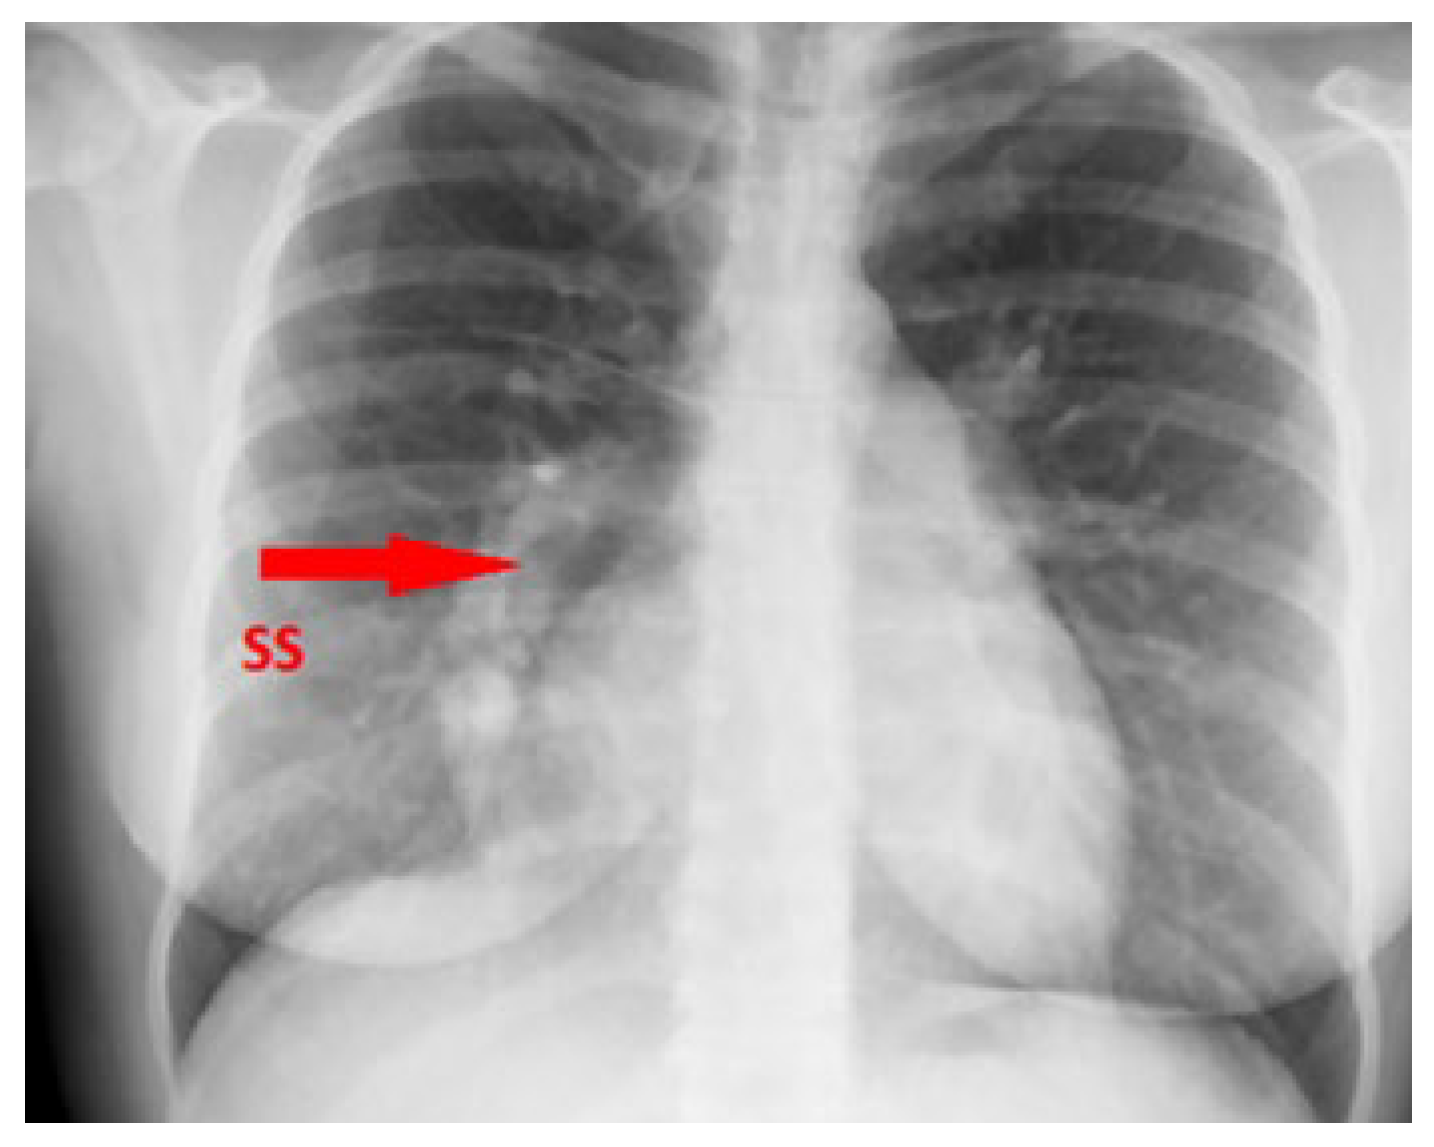

Chest X-ray demonstrated the typical right-sided curvilinear opacity with paracardial extension known as “scimitar sign” (Figure 2).

Figure 2. Chest X-ray showing the scimitar sign. SS (arrow): scimitar sign.